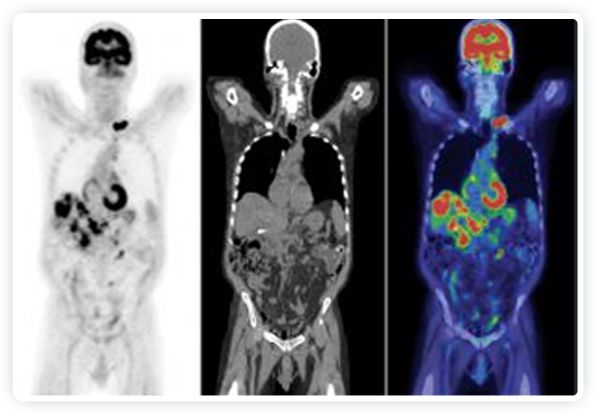

正電子發(fā)射斷層掃描(PET)是癌癥檢測中已建立的成像標(biāo)準(zhǔn),與其他成像方式相比,PET能提供高靈敏度和特異性的圖像。

到目前為止,放射腫瘤學(xué)中(使用的圖像主要是結(jié)構(gòu)性的,而PET圖像可以提供生物學(xué)信息。通過使用注射示蹤劑,例如18-FDG,PET可以描繪腫瘤的代謝活性,使其“點亮”。(FDG是用于可視化癌癥代謝的最廣泛使用的示蹤劑。與正常組織相比,腫瘤細胞保留更高水平的FDG。)不同的PET示蹤劑可以識別腫瘤的不同生物學(xué)特征,例如特定生物標(biāo)志物抗原(例如,PSMA)或甚至探測免疫系統(tǒng)本身(例如,PDL1表達或活化的T細胞)。

PET+放療共同治療

RefleXion將PET成像與立體定向放射治療相結(jié)合。在注射示蹤劑后,RefleXion的技術(shù)基于示蹤劑信號實時地在一個或多個目標(biāo)上引導(dǎo)治療性X射線。使用這種專有方法,RefleXion的平臺有可能比現(xiàn)有系統(tǒng)向癌癥病變提供更高劑量的輻射,并改善周圍健康組織的保護。